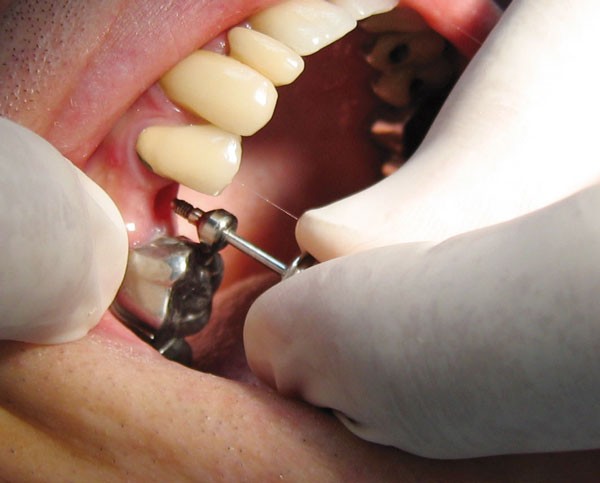

Le praticien s’assurera de la bonne intégration de l’implant avant la prise d’empreinte après examen clinique et radiographique (fig. 1).

Dépose de la vis de cicatrisation (fig. 4) : l’assistante présente au praticien l’embout du tournevis adapté à la tête de vis de cicatrisation (fig. 5).

Puis le tournevis est calé sur l’embout (fig. 6) et la vis est retirée (fig. 7).